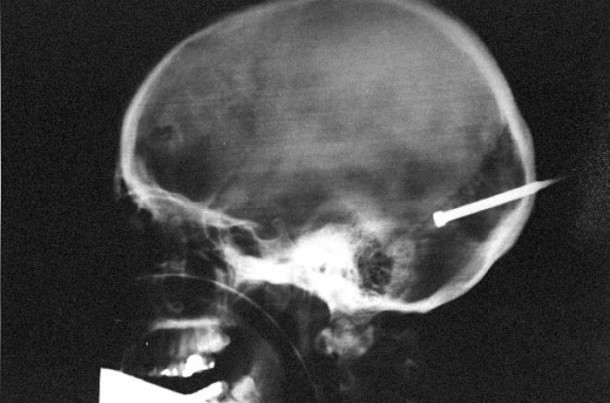

33 radiographies qui prouvent que les gens font des choses douteuses avec leur corps !